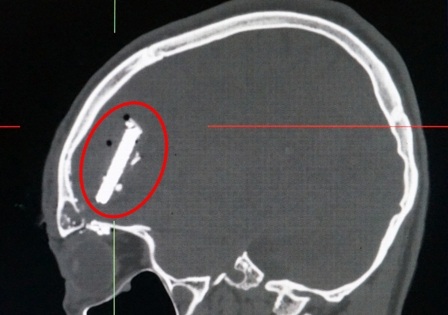

Các bác sĩ khoa Cấp cứu nhanh chóng xử lý vết thương, thực hiện các cận lâm sàng cần thiết. Kết quả CT 160 lát cắt dựng 3D xác định bệnh nhân bị vỡ xương trán trái, vỡ trần hốc mắt trái, có dị vật kích thước khoảng 28x43x11mm ghim vào vùng não trái gây xuất huyết não, tụ khí nội sọ quanh dị vật.

Ê kíp các bác sĩ Ngoại thần kinh kết hợp với các bác sĩ Gây mê hồi sức tiến hành mở sọ, làm sạch vết thương, cầm máu vỏ não, vén tách nhu mổ não. Các bác sĩ lấy được dị vật là một mẩu lưỡi cưa và nhiều mảnh xương vỡ. Sau đó, các bác sĩ cầm máu nhu mô não, xử lý xoang trán bị vỡ và kết thúc cuộc phẫu thuật thành công.